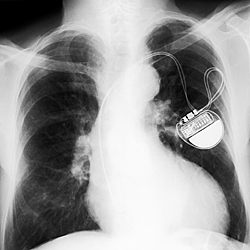

Pacemakers, like the implanted one shown in this image, are among the low-power devices that could be affected by new NIST findings about transistor noise. The findings indicate unforeseen problems could crop up as transistors grow smaller and run on less power, potentially impacting cell phones and laptops as well. [Credit: Shutterstock; copyright Dario Sabljak]